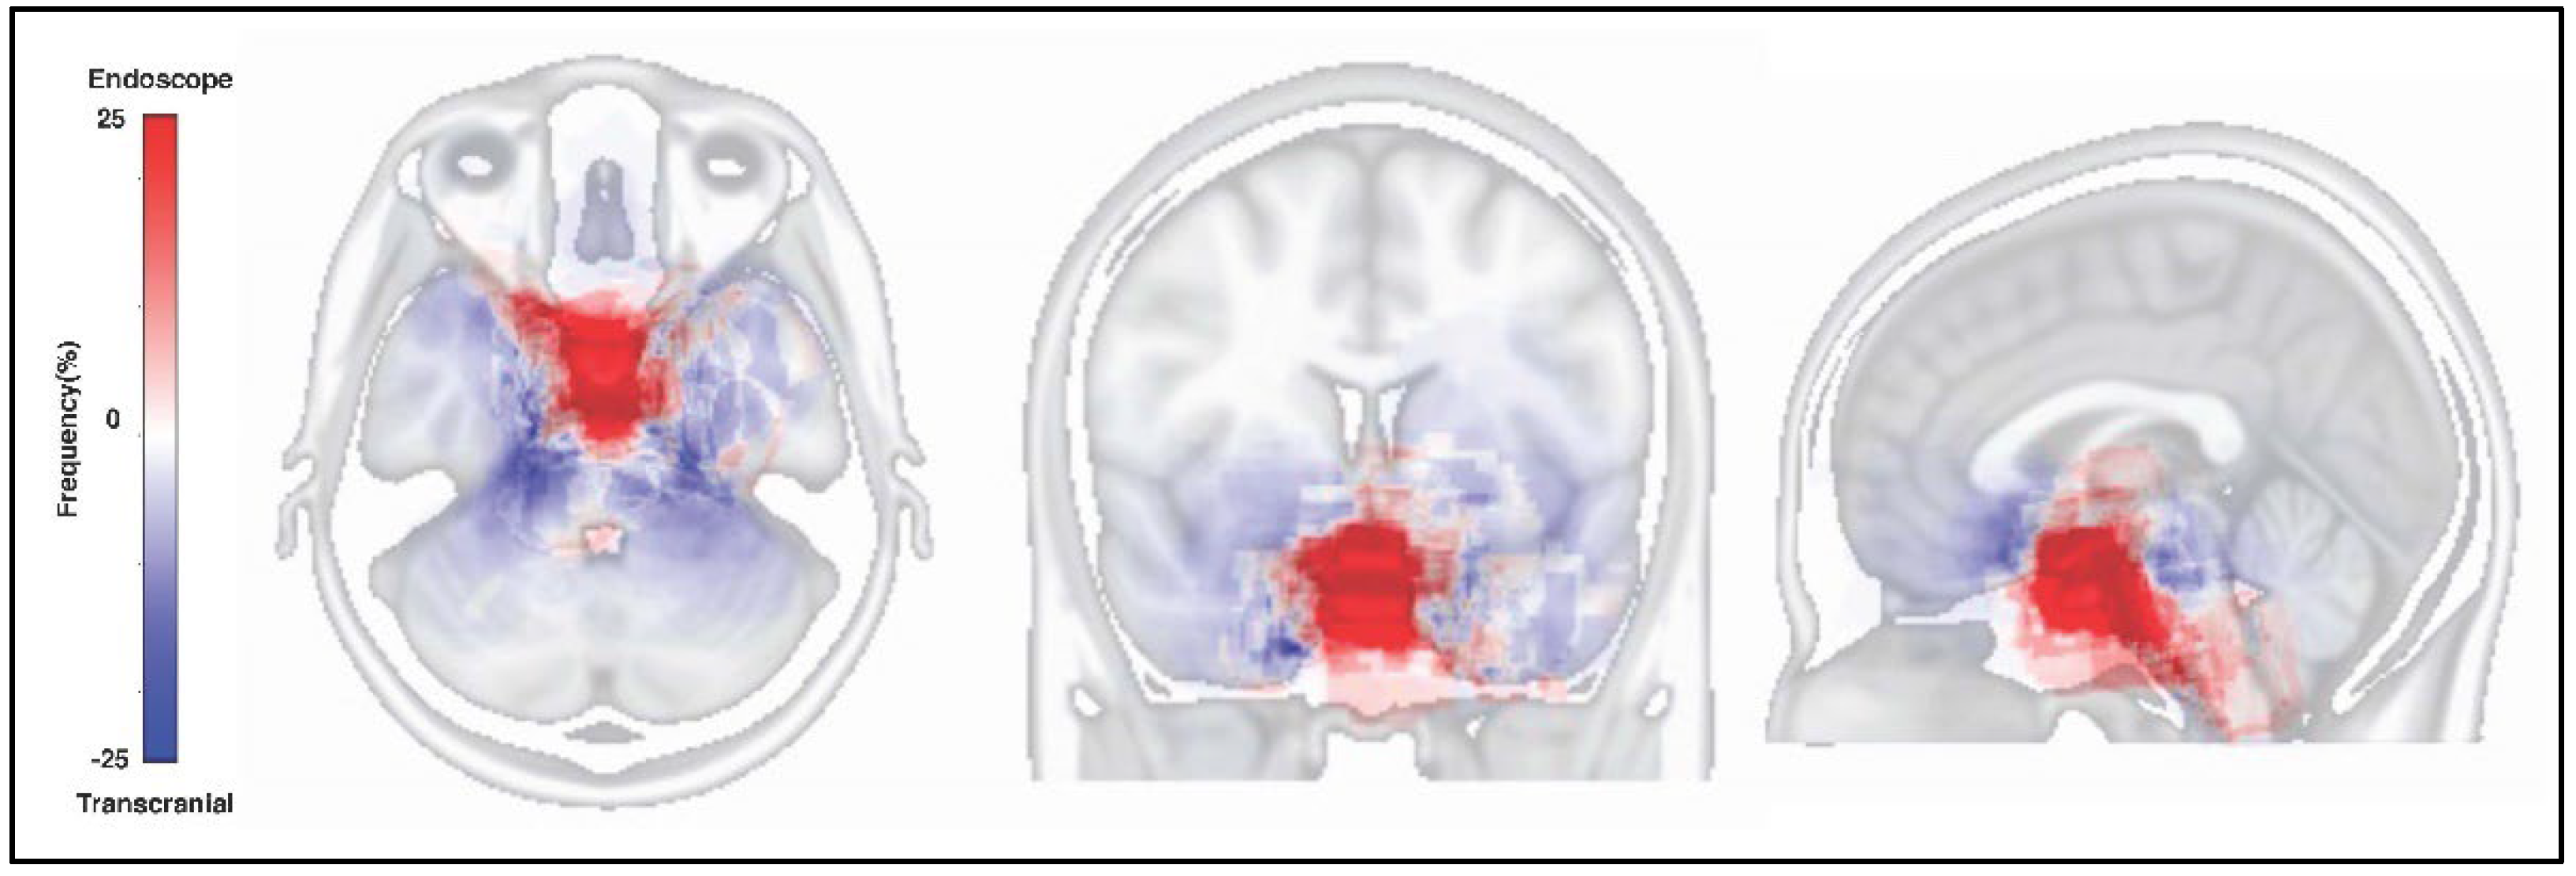

3.7. Tumor Resected Map by Both Approaches

4.3. Voxel-Based-Lesion Mapping for Skull Base Meningiomas